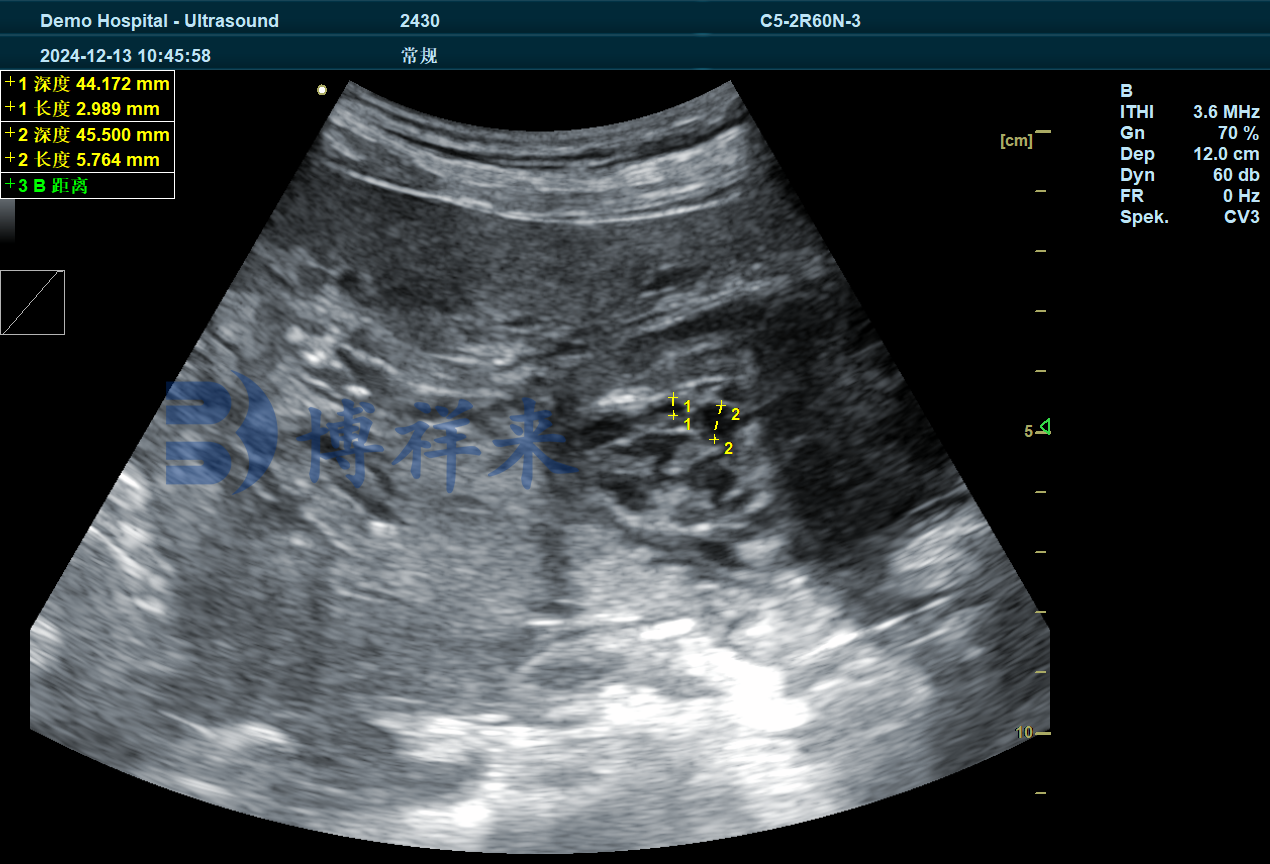

下面超声图像是使用 BXL-DZ20 配合大凸探头检测的母猪卵巢发育情况超声图像